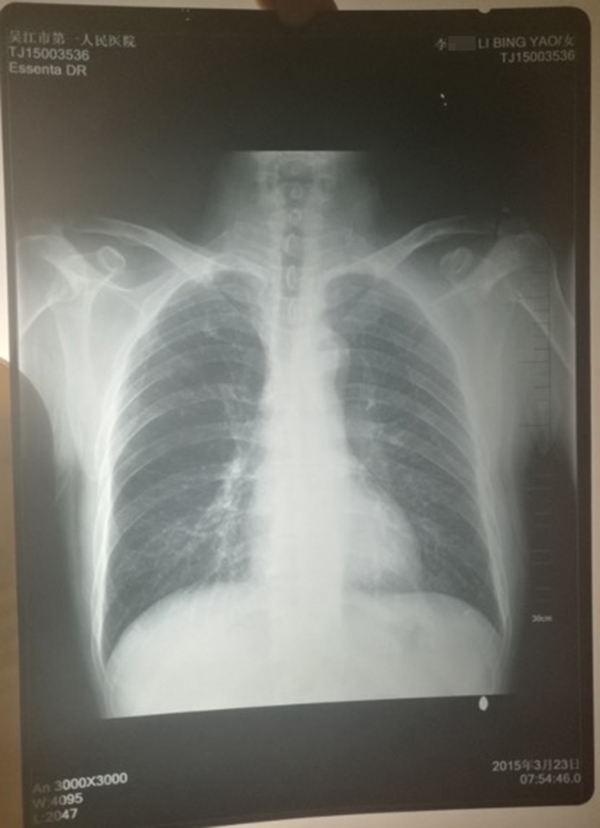

医院提供的计建宏的“真实胸片”,写有姓名“李某某”。 受访人供图

计云强称,吴江区第一人民医院曾提供一份印有“李某某”姓名的胸片,并称该胸片才是计建宏的“真实影像结果”。

对于“李某某”姓名的胸片,上述吴姓主任称,经过医院核查,两份胸片的结果都是“正常”的,“如果结果是不一样的话,那么问题就大了,但是因为是一样的结果,所以不能认为是‘漏诊’或‘误诊’。”